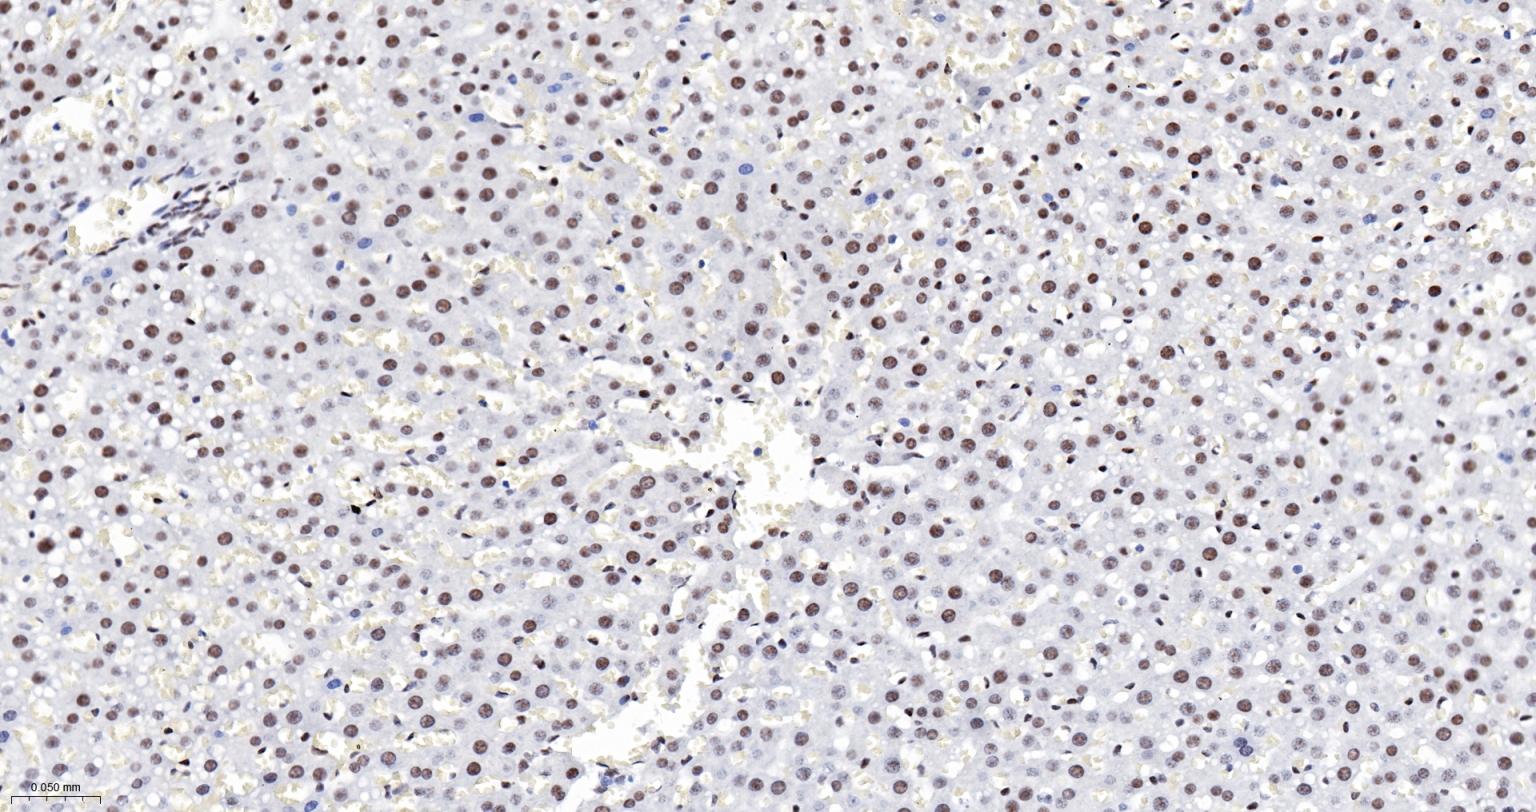

Paraformaldehyde-fixed, paraffin embedded Human Liver; Antigen retrieval by boiling in sodium citrate buffer (pH6.0) for 15 min; The section was incubated with DDX9 Monoclonal Antibody, Unconjugated (bsm-61787R) at 1:200 overnight at 4°C, followed by conjugation to the bs-0295G-HRP and DAB (C-0010) staining.